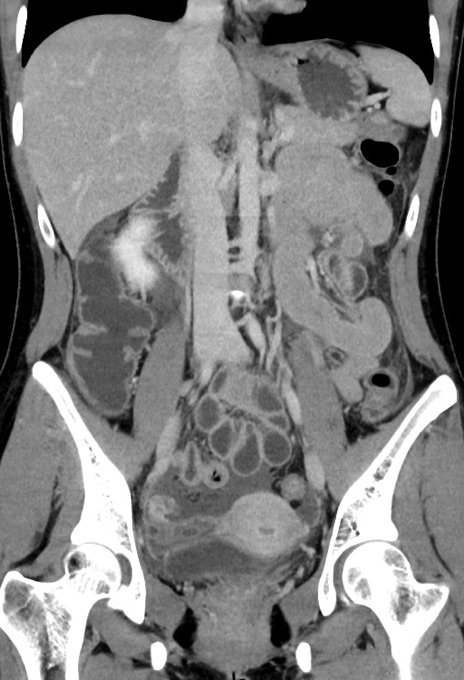

症例17(冠状断像)

【症例】20歳代女性

【主訴】嘔吐、下腹部痛

【現病歴】昨日夕食後に嘔吐し下腹部痛が出現。本日になっても嘔吐持続し改善しないため来院。

【身体所見】意識清明、BT 37.2℃、BP 108/67mmHg、腹部:平坦、やや硬、下腹部正中から右にかけて圧痛あり、反跳痛軽度あり、tapping pain(+)。

【データ】WBC 13600、CRP 14.94

横断像